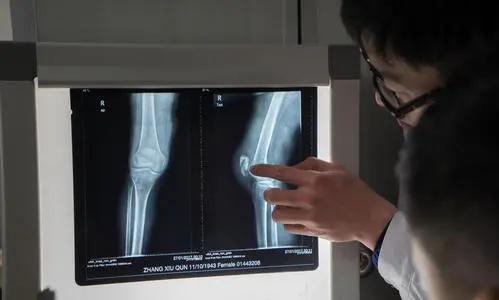

人们去医院看病时,医生经常会开单子,让患者去放射科拍个片子,这片子就是医用胶片,上面承载着医疗影像图文信息。

过去,医院检查胸部和骨骼主要采用X光照射,俗称“拍片”,影像是黑白的,所拍X光胶片一般由感光乳剂层、片基、保护层、底层(结合层)组成。后来发展起来的医用彩色胶片结构比较复杂,一般分为保护层、上层感光乳剂、滤光层、隔层、中下层感光乳剂、结合层、片基、抗光晕静电层。

早期的胶片是非数字化的,和普通的胶卷一样,需要在暗室内经过反转底片,在显影液和定影液的相互作用下成像,成像的银盐胶片又叫“湿片”。后来,随着B超、双源CT、螺旋CT、超导核磁共振等大型数字影像设备的发展,可以直接采用数字化技术一次成像,也被称为干式胶片。

目前医用胶片多为化学成像胶片。所谓化学成像,是指通过一系列化学反应在胶片介质上形成最终影像。这种胶片表面是均匀涂抹的碳粉,对日光不敏感,可在明室操作,也不需化学处理。常见的化学成像胶片有激光干式胶片、热敏干式胶片,胶片在干式打印机内成像后,原有的两层保护膜脱掉,在碳粉层图像两面再各压一层保护膜。

随着数字化技术的普及,各大医院都配有胶片打印自助终端,也称医院自助取片机,是基于医院影像胶片打印、影像诊断报告的打印于一体的医疗自助服务终端设备,适用放射科所有影像设备的输出,如CR、DR、CT、MRI、DSA等数字影像设备。病人检查完后可以刷卡自主打印影像胶片和诊断报告。